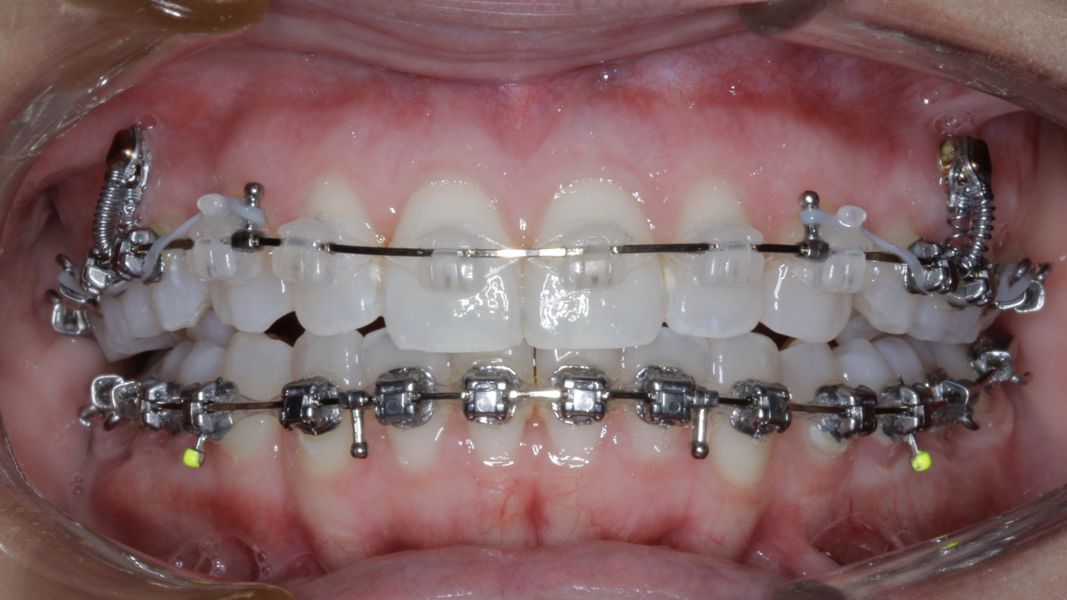

New Age orthodontics and orthopaedics with temporary anchorage devices